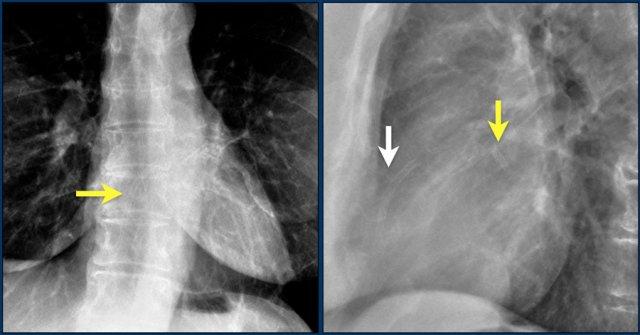

Các van tim được xác định rõ nhất trên phim X-quang tư thế nghiêng.

Van động mạch chủ và van động mạch phổi nằm phía trên đường kẻ từ mỏm tim đến nền tim, trong khi van hai lá và van ba lá nằm phía dưới đường này.

Hình ảnh thể hiện vị trí van tim bình thường trên phim X-quang ngực thẳng (PA) và nghiêng.

Trên phim X-quang ngực tư thế nghiêng, van động mạch chủ và van động mạch phổi nằm phía trên đường kẻ từ nền tim đến mỏm tim, còn van ba lá và van hai lá nằm phía dưới đường này.